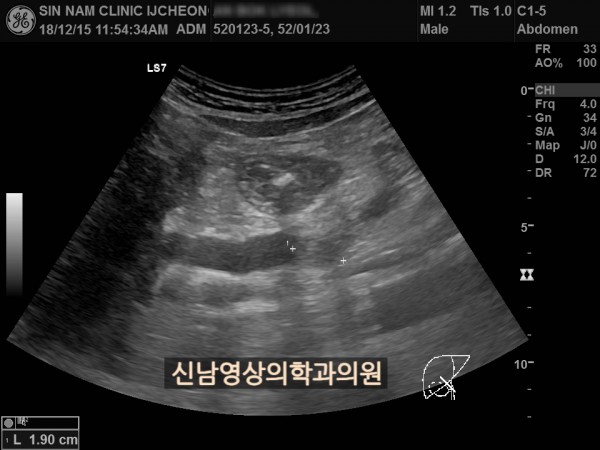

상복부검진

50~60대 발병률이 높은 담관암, 담도암, 상복부 초음파, 영상의학과 전문의